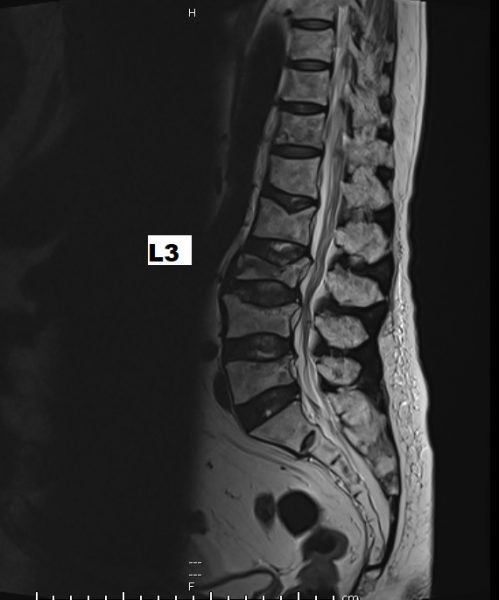

磁力共振扫描显示,阿贵嫂的腰椎崩塌确有恶化趋向,主要神经管也受到压迫。我决定为她进行微创水泥椎体成形手术(Cement vertebroplasty),在X光透视引导下,将骨水泥注入崩塌的第3节腰椎,支撑受损的椎体,同时也做了椎板切除手术,舒缓受压的神经线。

崩塌惡化,主要神經管也受到壓迫。-499x600.jpg)